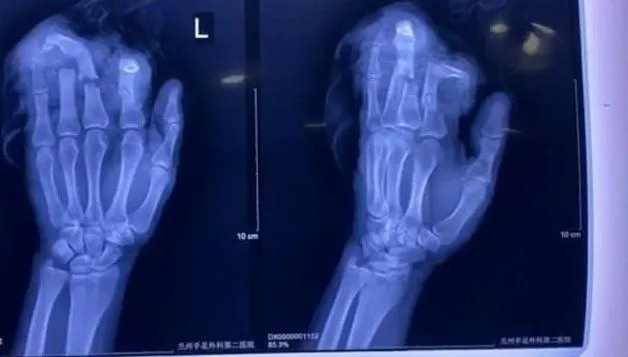

"ผมไม่อยากลงไม้ลงมือกับเมียผม เพราะมันเป็นเรื่องที่ไม่ควรทำ ก็เลยคว้าปังตอที่แขวนอยู่ด้านหลังมาสับนิ้วมือซ้ายผมอย่างแรง และก็อย่างที่ทุกคนคิด มันเป็นการกระทำที่โง่เขลามาก" ด้านหมอผู้ฟื้นคืนชีพมือซ้ายให้เขาระบุว่า นิ้วมือข้างซ้ายของเขาขาดเกือบทั้งหมด ทั้งนิ้วชี้ นิ้วกลาง นิ้วนางและนิ้วก้อย บาดแผลลึกถึงชั้นกระดูก แต่กระนั้นศัลยแพทย์ผู้เชี่ยวชาญมือและเท้า ก็สามารถต่อนิ้วทั้งหมดกลับเข้าที่ได้

แต่ถึงอย่างนั้น คุณหมอก็ได้บอกว่า แม้เขาจะต่อนิ้วกลับทั้งหมดให้ได้ แต่คนไข้จะไม่สามารถใช้งานมือข้างนี้ได้เต็มประสิทธิภาพ 100% ก่อนถูกตัดแน่นอน เพราะมีบางส่วนที่เสียหายเกินเยียวยา ตอนนี้หนุ่มดังกล่าวได้พักฟื้นอยู่ที่โรงพยาบาล โดยมีภรรยาคอยดูแลอย่างใกล้ชิด และทั้งคู่ก็สารภาพว่า ตอนนี้รู้สึกผิดต่อกันเป็นอย่างมาก เสียใจที่การใช้อารมณ์ใส่กันจะนำมาซึ่งการเจ็บตัวของสามีเช่นนี้ ยังไงชีวิตคู่มันก็ต้องมีกระทบกระทั่งกันบ้างล่ะนะ ก็ขอให้ใช้เหตุผลคุยกันเคลียร์กันจะดีกว่า เพราะความรุนแรงไม่ใช่ทางแก้ปัญหาที่ดีที่สุด...